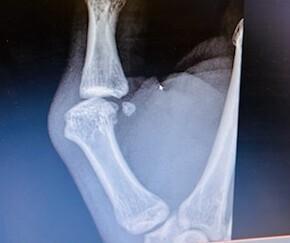

Un militaire consulte pour un traumatisme indirect de l’articulation métacarpo-phalangienne du pouce en varus-flexion lors de la manipulation d’une poignée de container. Il décrit une sensation de craquement, de déboîtement, puis une remise en place spontanée. L’articulation est œdématiée, avec déviation axiale (fig. 1 et 2). L’examen clinique révèle une douleur localisée au niveau du ligament collatéral radial avec un bâillement articulaire, signant une instabilité. La radiographie ne montre pas de fracture mais une subluxation collatérale ulnaire (fig. 3).